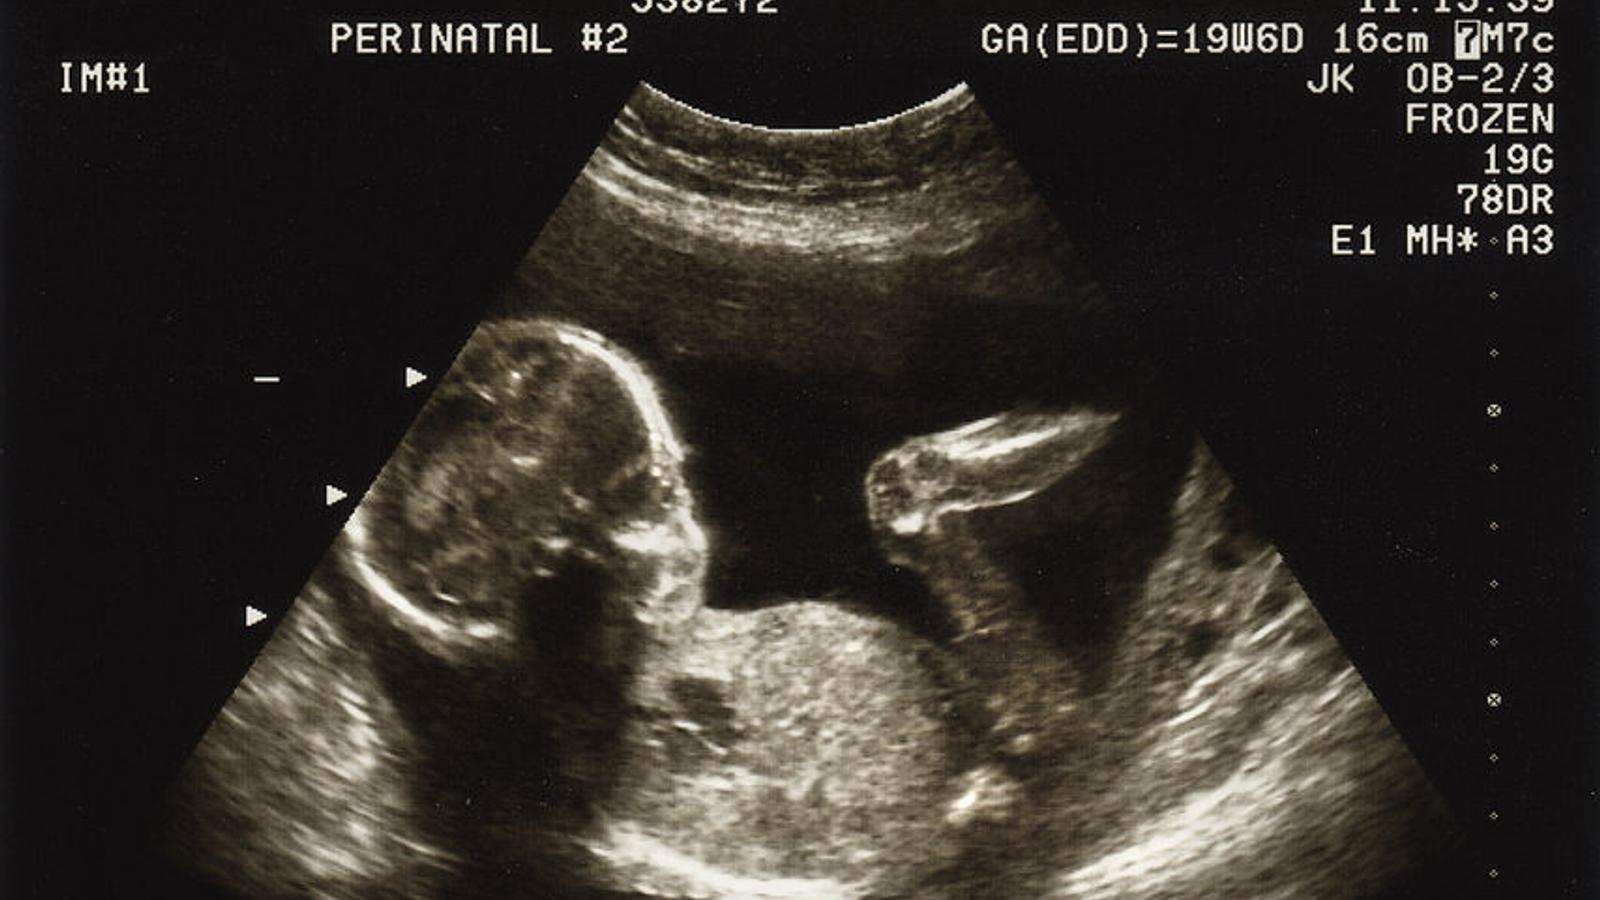

Ultraschallbild eines Babys

Mit einer Nackenfaltenmessung kann das Risiko einer Chromosomenfehlbildung beim Baby eingeschätzt werden.

Eine Nackenfaltenmessung (NT-Screening, Nackendickemessung) ist eine spezielle Form der Ultraschalluntersuchung.